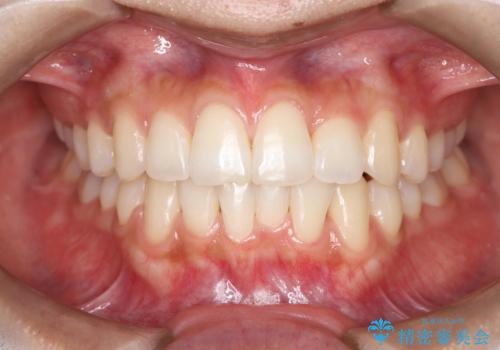

治療計画をしっかり立て、歯の移動量や力のコントロールを最適化することで、約1年という短期間で矯正治療を終了することができました。

「矯正は時間がかかる」というイメージをお持ちの方も多いですが、症例によっては、非抜歯でも短期間で改善が可能な場合があります。

治療後は歯並び・かみ合わせともに大きく改善し、患者様にも大変ご満足いただけました。